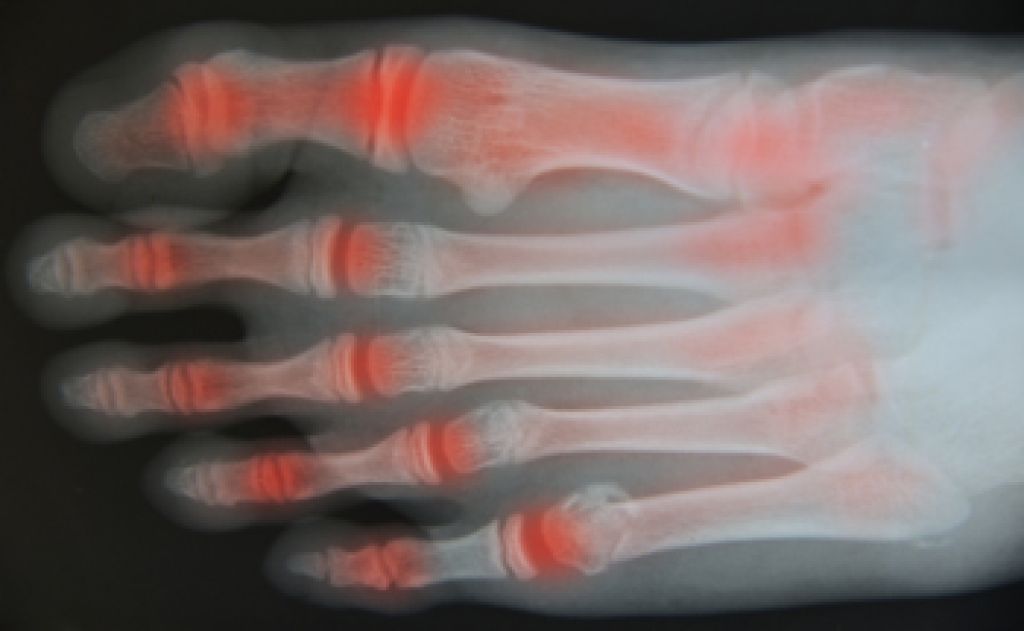

Osteoarthritis is a degenerative joint condition that occurs when cartilage wears down over time, leading to pain and stiffness. In the feet, it often affects joints in the toes and midfoot, making walking uncomfortable. Causes include aging, excess body weight, genetic predisposition, and other forms of arthritis that contribute to joint damage. Symptoms include pain, swelling in foot joints, reduced flexibility, and discomfort that may worsen at night. Persistent foot pain can interfere with daily activities and overall quality of life. A podiatrist can diagnose the condition, recommend supportive footwear, provide custom orthotics, and develop a treatment plan to reduce pain and improve mobility. If you are experiencing ongoing foot discomfort or swelling, it is suggested that you consult a podiatrist who can offer effective relief and management solutions.

Arthritis is a term that is commonly used to describe joint pain. The condition itself can occur to anyone of any age, race, or gender, and there are over 100 types of it. Nevertheless, arthritis is more commonly found in women compared to men, and it is also more prevalent in those who are overweight. The causes of arthritis vary depending on which type of arthritis you have. Osteoarthritis for example, is often caused by injury, while rheumatoid arthritis is caused by a misdirected immune system.

Arthritic symptoms range in severity, and they may come and go. Some symptoms stay the same for several years but could potentially get worse with time. Severe cases of arthritis can prevent its sufferers from performing daily activities and make walking difficult.